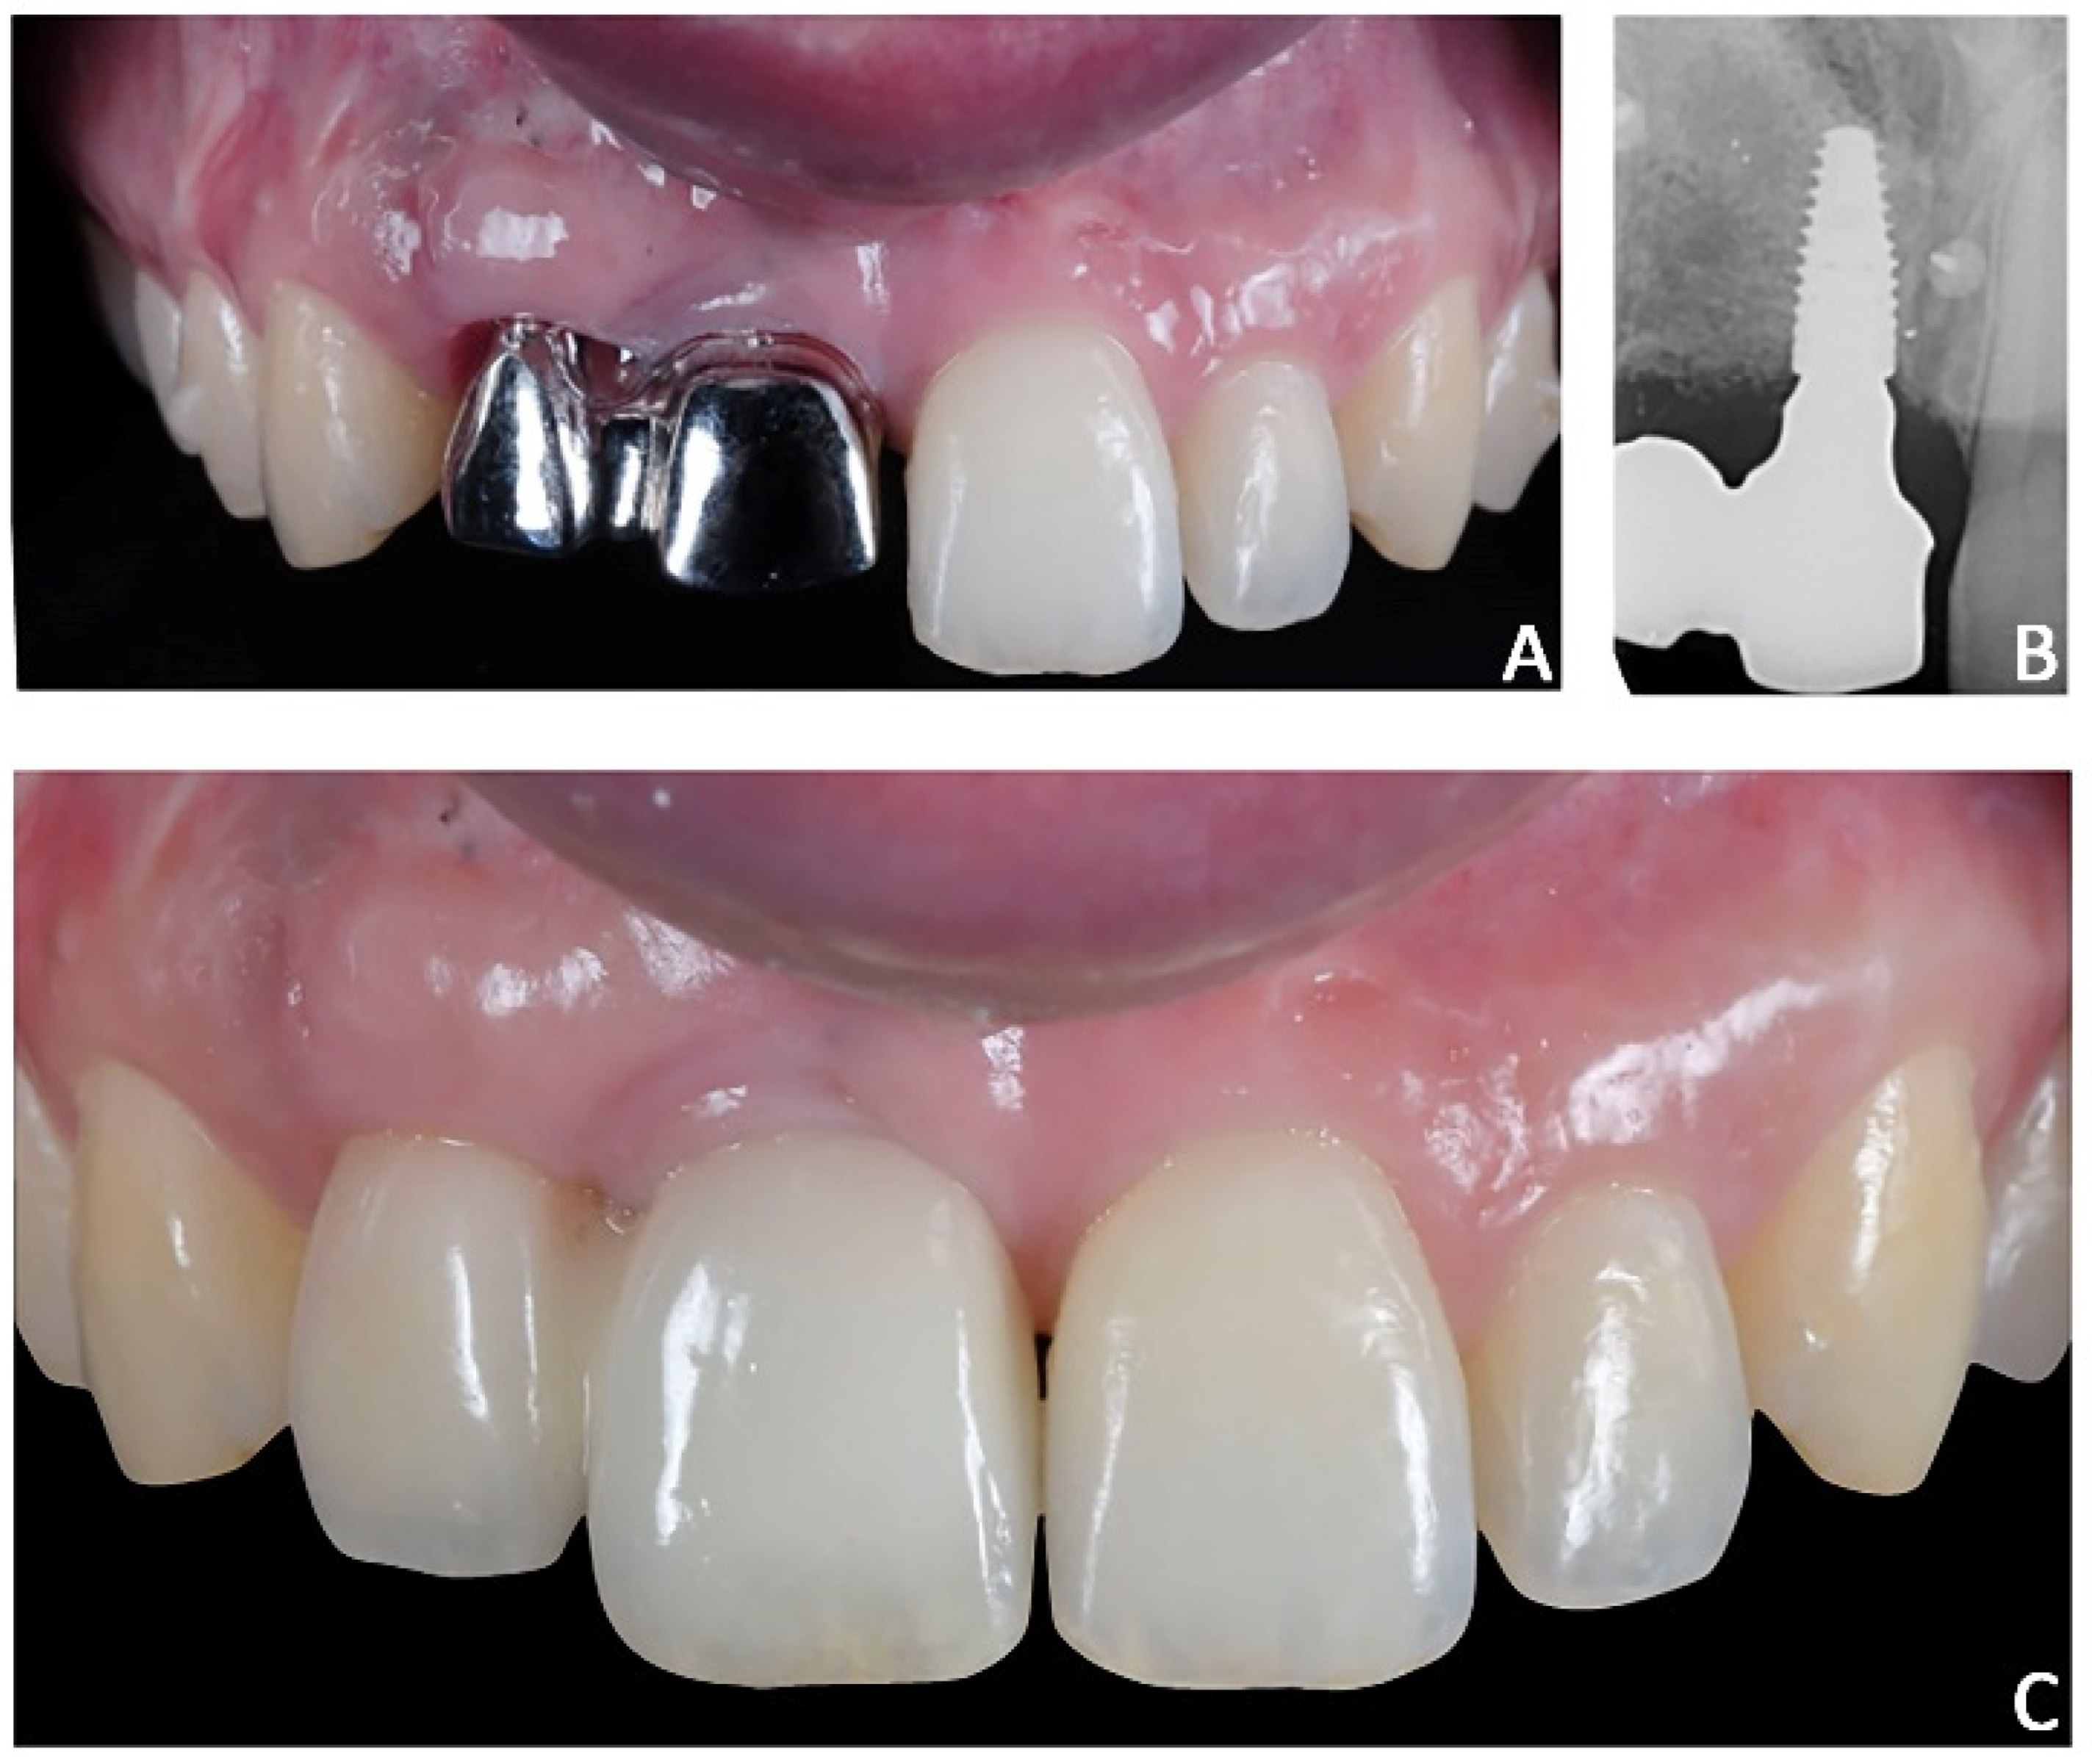

Final prosthetic rehabilitation. After orthodontic treatment, two intra-oral scans were registered: (1) an intra-oral scan with the position of the implant and surrounding soft tissues and (2) an intra-oral scan with the provisional prosthesis. The two files were sent to the laboratory and would replicate the relationships between the soft tissues and the temporary prosthesis in the final prosthesis. After prototyping the 3D model of the maxillary arch, the lab technician projected a milled cobalt-chrome structure that was veneered with feldspathic porcelain (Figure 14).

Figure 14. Case 2. Final prosthesis using milled cobalt-chrome structure and feldspathic porcelain. (A) Milled cobalt-chrome structure; (B) radiographic evaluation; (C) prosthesis veneered with feldspathic porcelain.